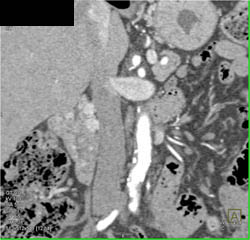

Bulky Gastric Cancer With Ulceration- Multiple Renderings